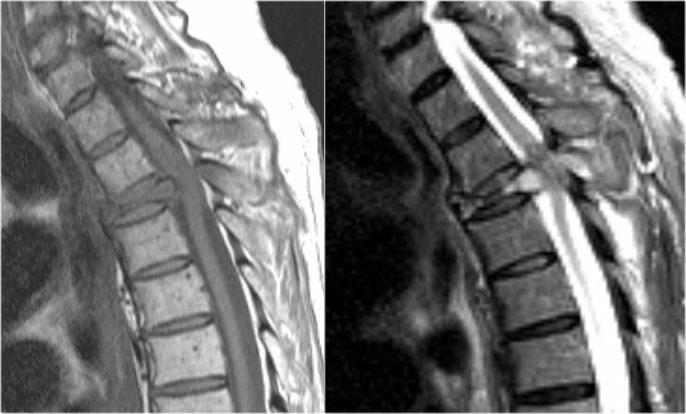

Hình ảnh bên trái của một trẻ em nhập viện với viêm thần kinh thị giác một bên.

Hình ảnh não hoàn toàn bình thường.

Tiếp tục xem MRI cột sống.

Những bệnh nhân có một đợt viêm thần kinh thị giác hoặc viêm tủy và có kết quả xét nghiệm NMO-IgG dương tính có nguy cơ cao tiến triển thành toàn bộ phổ bệnh NMO.

Một tháng sau, trẻ này nhập viện với bệnh tủy cắt ngang cấp tính, tức là các triệu chứng hai bên.

Hình ảnh cho thấy tín hiệu bất thường trong tủy sống kèm phù nề và ngấm thuốc nhẹ.

U tế bào hình sao (astrocytoma) hoàn toàn có thể biểu hiện với hình ảnh tương tự, tuy nhiên dựa vào tiền sử viêm thần kinh thị giác và bệnh tủy cấp tính, chúng ta không nghĩ đến khối u.

Trường hợp này được xác định là NMO và xét nghiệm Ig cho NMO dương tính.

Hình ảnh bên trái của một trẻ vị thành niên với bệnh sử điển hình:

- Ba tuần sau nhiễm trùng đường hô hấp, khởi phát đột ngột các triệu chứng thần kinh.

-

Loạn vận ngôn, khó nuốt, liệt tứ chi.

Rối loạn vận nhãn và rối loạn ý thức.

Bệnh sử lâm sàng này điển hình cho ADEM.

Thông thường não cũng bị tổn thương.

30% trường hợp có tổn thương tủy sống.

Các đặc điểm hình ảnh trong trường hợp này cũng rất điển hình.

Có hình ảnh phù nề và tổn thương tủy tương tự như trong viêm tủy ngang (TM) và không có ngấm thuốc.

Tiếp tục xem các hình ảnh của não.

Trước tiên hãy quan sát các hình ảnh não và xác định điểm khác biệt so với tổn thương trong MS.

Những đặc điểm điển hình cho ADEM và ít gặp trong MS là:

- Tổn thương lan rộng vùng cầu não.

- Tổn thương hạch nền.

Hình ảnh MRI theo dõi cho thấy tủy sống đã trở về bình thường.